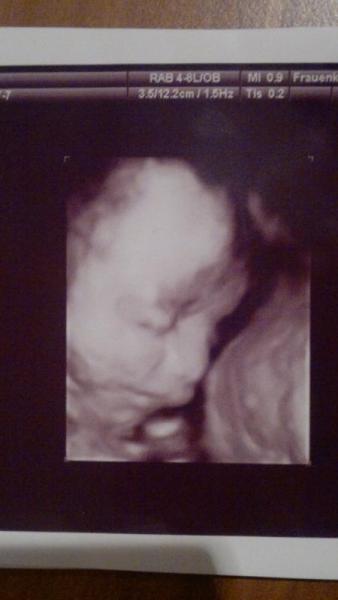

Hallo Mädels, ich weiß gar net wo ich anfangen soll.... Gestern war so ziemlich der schlimmste Tag der ganzen SS! Ich hatte so unglaubliche Schmerzen den ganzen Tag...Kaum saß oder stand ich mehr als ein paar Minuten gings los...ich hatte mehrere male echt heulen müssen...wie soll ich das nur durchstehen bis zum Ende??? Ich hab gestern auch solche Angst vor der Geburt bekommen...hab wirklich Angst dass ich es nicht schaffe..hab so Angst vor den Schmerzen!!! Ich hab mit 14 Jahren meinen Sohn normal also spontan auf die Welt gebracht in ner halben Std. das war 2003 und 2010 meine Tochter per KS ... Wenn ichs mit 14 geschafft hab dann werd ichs doch jetzt mit 23 auch schaffen oder? Ich hab wirklich Angst und komm mir echt lächerlich vor beim dritten noch Angst zu haben oder findet ihr das normal? Ich bin auch scho so geschlaucht von den ständigen Wehen...seit der 18SSw bin ich dauernd im KH wegen Wehen und so....es geht mir imme rmieser...weiß gar nicht ann ich nen Tag hatte an dem es mir gut ging... naja jetzt muss ich nachmittag heut eh zum FA weil ich ja sehr viel bis zu viel Fruchtwasser hab und das kontrolliert werden muss.... Ich hab auch kaum mehr GBMH wegen der Konisation damals und das zusätzliche Gewicht durchs zusätzliche Fruchtwasser ist halt nicht gerade förderlich jetzt... bin gespannt und hab Angst dass sich der GbMH wieder verkürzt hat! Ich wills noch bis 4 wochen vor dem ET schaffen -.- Oh Mädels...Ich wills doch auch genießen und freu mich ja auch auf meine Puppe...aber mir gehts langsam echt net mehr gut... LG Christina P.S.: Ich war Dienstag beim 3D Ultraschall....soooo süss.... häng euch ein Bild mit an

So,noch ein zweites Bildchen meiner Prinzessin